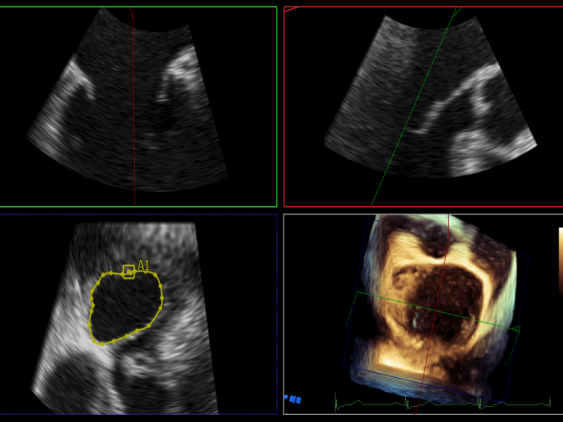

3D:P1区脱垂并腱索断裂,部分AC受累,Width:11.4mm

3d确认夹子位置在P1区

3d-color确认残余分流情况